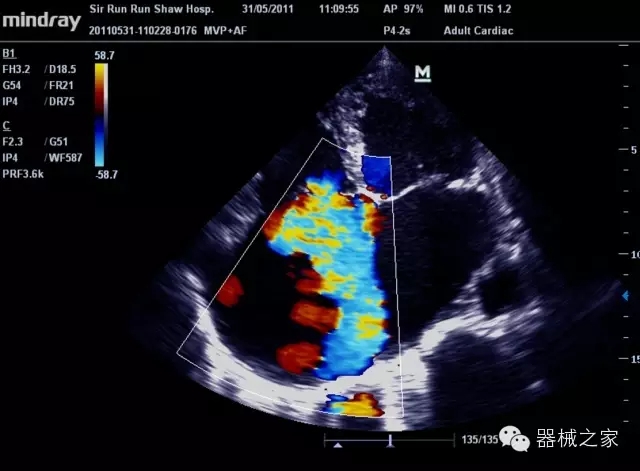

經(jīng)典產(chǎn)品:M7(星鉆)

臨床圖片賞析

產(chǎn)品特點

·裝載有采用Multi-Core多核處理的非嵌入式平臺,成像效率大大提高,并且能夠給用戶帶來高速、多任務(wù)并行信號處理體驗;

·優(yōu)秀的圖像效果、強大的功能體驗、豐富的探頭選擇、合理的便攜式設(shè)計,全中文顯示及病人管理界面,使得M7在任何場合、任何時候都能快速響應(yīng)更好的心血管、腹部、婦產(chǎn)、小器官等常規(guī)超聲檢查以及肌骨、神經(jīng)、顱腦、術(shù)中等新興領(lǐng)域的使用需求;

8倍波束并行處理系統(tǒng)

·在便攜式緊湊平臺上采用更多倍波束并行接收信號處理模式,無論二維還是彩色血流圖像狀態(tài)下,擁有更靈敏的回波頻移捕獲能力,大大提高時間分辨率,尤其使得心血管表現(xiàn)更為突出;

PSHI?寬帶頻移諧波技術(shù)

·在普通組織諧波的基礎(chǔ)上,通過精確控制的波束形成器,發(fā)射兩組具有相位偏差反向的信號,并采用并行信號處理,數(shù)字化合成并采樣回波信號,在高靈敏度的濾波器的處理過程中獲取更純凈的諧波信號,使圖像具有更加出眾的細(xì)節(jié)分辨率;

iClear®+iBeam?

·智能化按線復(fù)合多角度獲取聲束的原始信號,配合智能化的斑點噪聲識別及控制處理技術(shù),整體提高組織結(jié)構(gòu)細(xì)節(jié)分辨率,任何時候都能快速響應(yīng),更好的滿足心血管的使用需求;